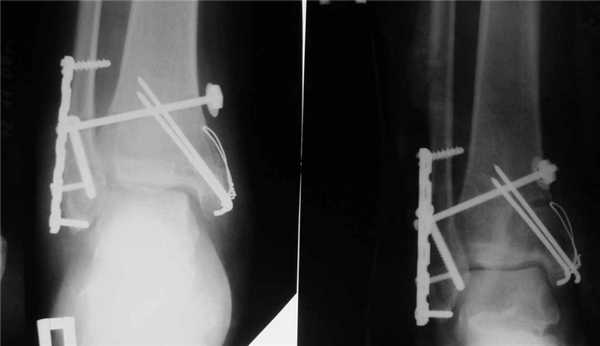

Открытая репозиция с внутренней фиксацией

Метод применяют для лечения сложных переломов, когда невозможна ручная репозиция отломков и удержание их в нужной позиции с помощью гипса. Чтобы сопоставить костные фрагменты и надежно зафиксировать их, используют погружные элементы и конструкции:

- болты-стяжки;

- винты;

- болты с клеммами-накладками;

- спицы Киршнера;

- болты с гибкой тягой;

- лавсановые ленты и прочее.

Открытая репозиция обеспечивает одномоментное точное сопоставление отломков и их надежную фиксацию. После операции нередко сохраняется ранняя опороспособность конечности, что позволяет нагружать ее вскоре после операции. И тем не менее многие специалисты уверены, что ни один из методов открытой репозиции не может обеспечить полной неподвижности костных фрагментов. Поэтому после операции пациентам требуется дополнительная гипсовая иммобилизация.

Оперативное сопоставление и фиксация отломков имеет и другие недостатки:

- Травмирование мягких тканей в месте проведения хирургического вмешательства.

- Риск развития инфекционных осложнений.

- Вероятность вторичных смещений отломков из-за несостоятельности фиксаторов.

- Высокая частота развития псевдоартрозов.